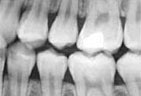

We use state of the art digital X-rays and digital cameras to help with an accurate diagnosis of any concerns. Digital X-rays use less radiation to get a diagnostic picture of your teeth and they help the environment by eliminating the use of chemicals to process the film.

Digital x-ray image